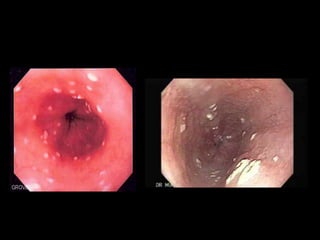

• Presentation:

• Oral candidiasis (thrush)

• Diaper rash.

• vulvovaginal candidiasis at puberty in females.

• Nail infection :leading to a darkened discoloration, thickening,

or erosion.

• intestinal mucosal candidiasis :lead to intermittent abdominal

pain and diarrhea.

Chronic mucocutaneous candidiasis CMC

• Retrosternal pain occurring in patients with

confirmed oral candidiasis suggests esophageal

candidiasis which may lead to stricture and

dysphagia.

• epithelial carcinoma of the oral mucosa, tongue or

esophagus with its high mortality is well described in

APS I patients with chronic mucosal candidiasis.